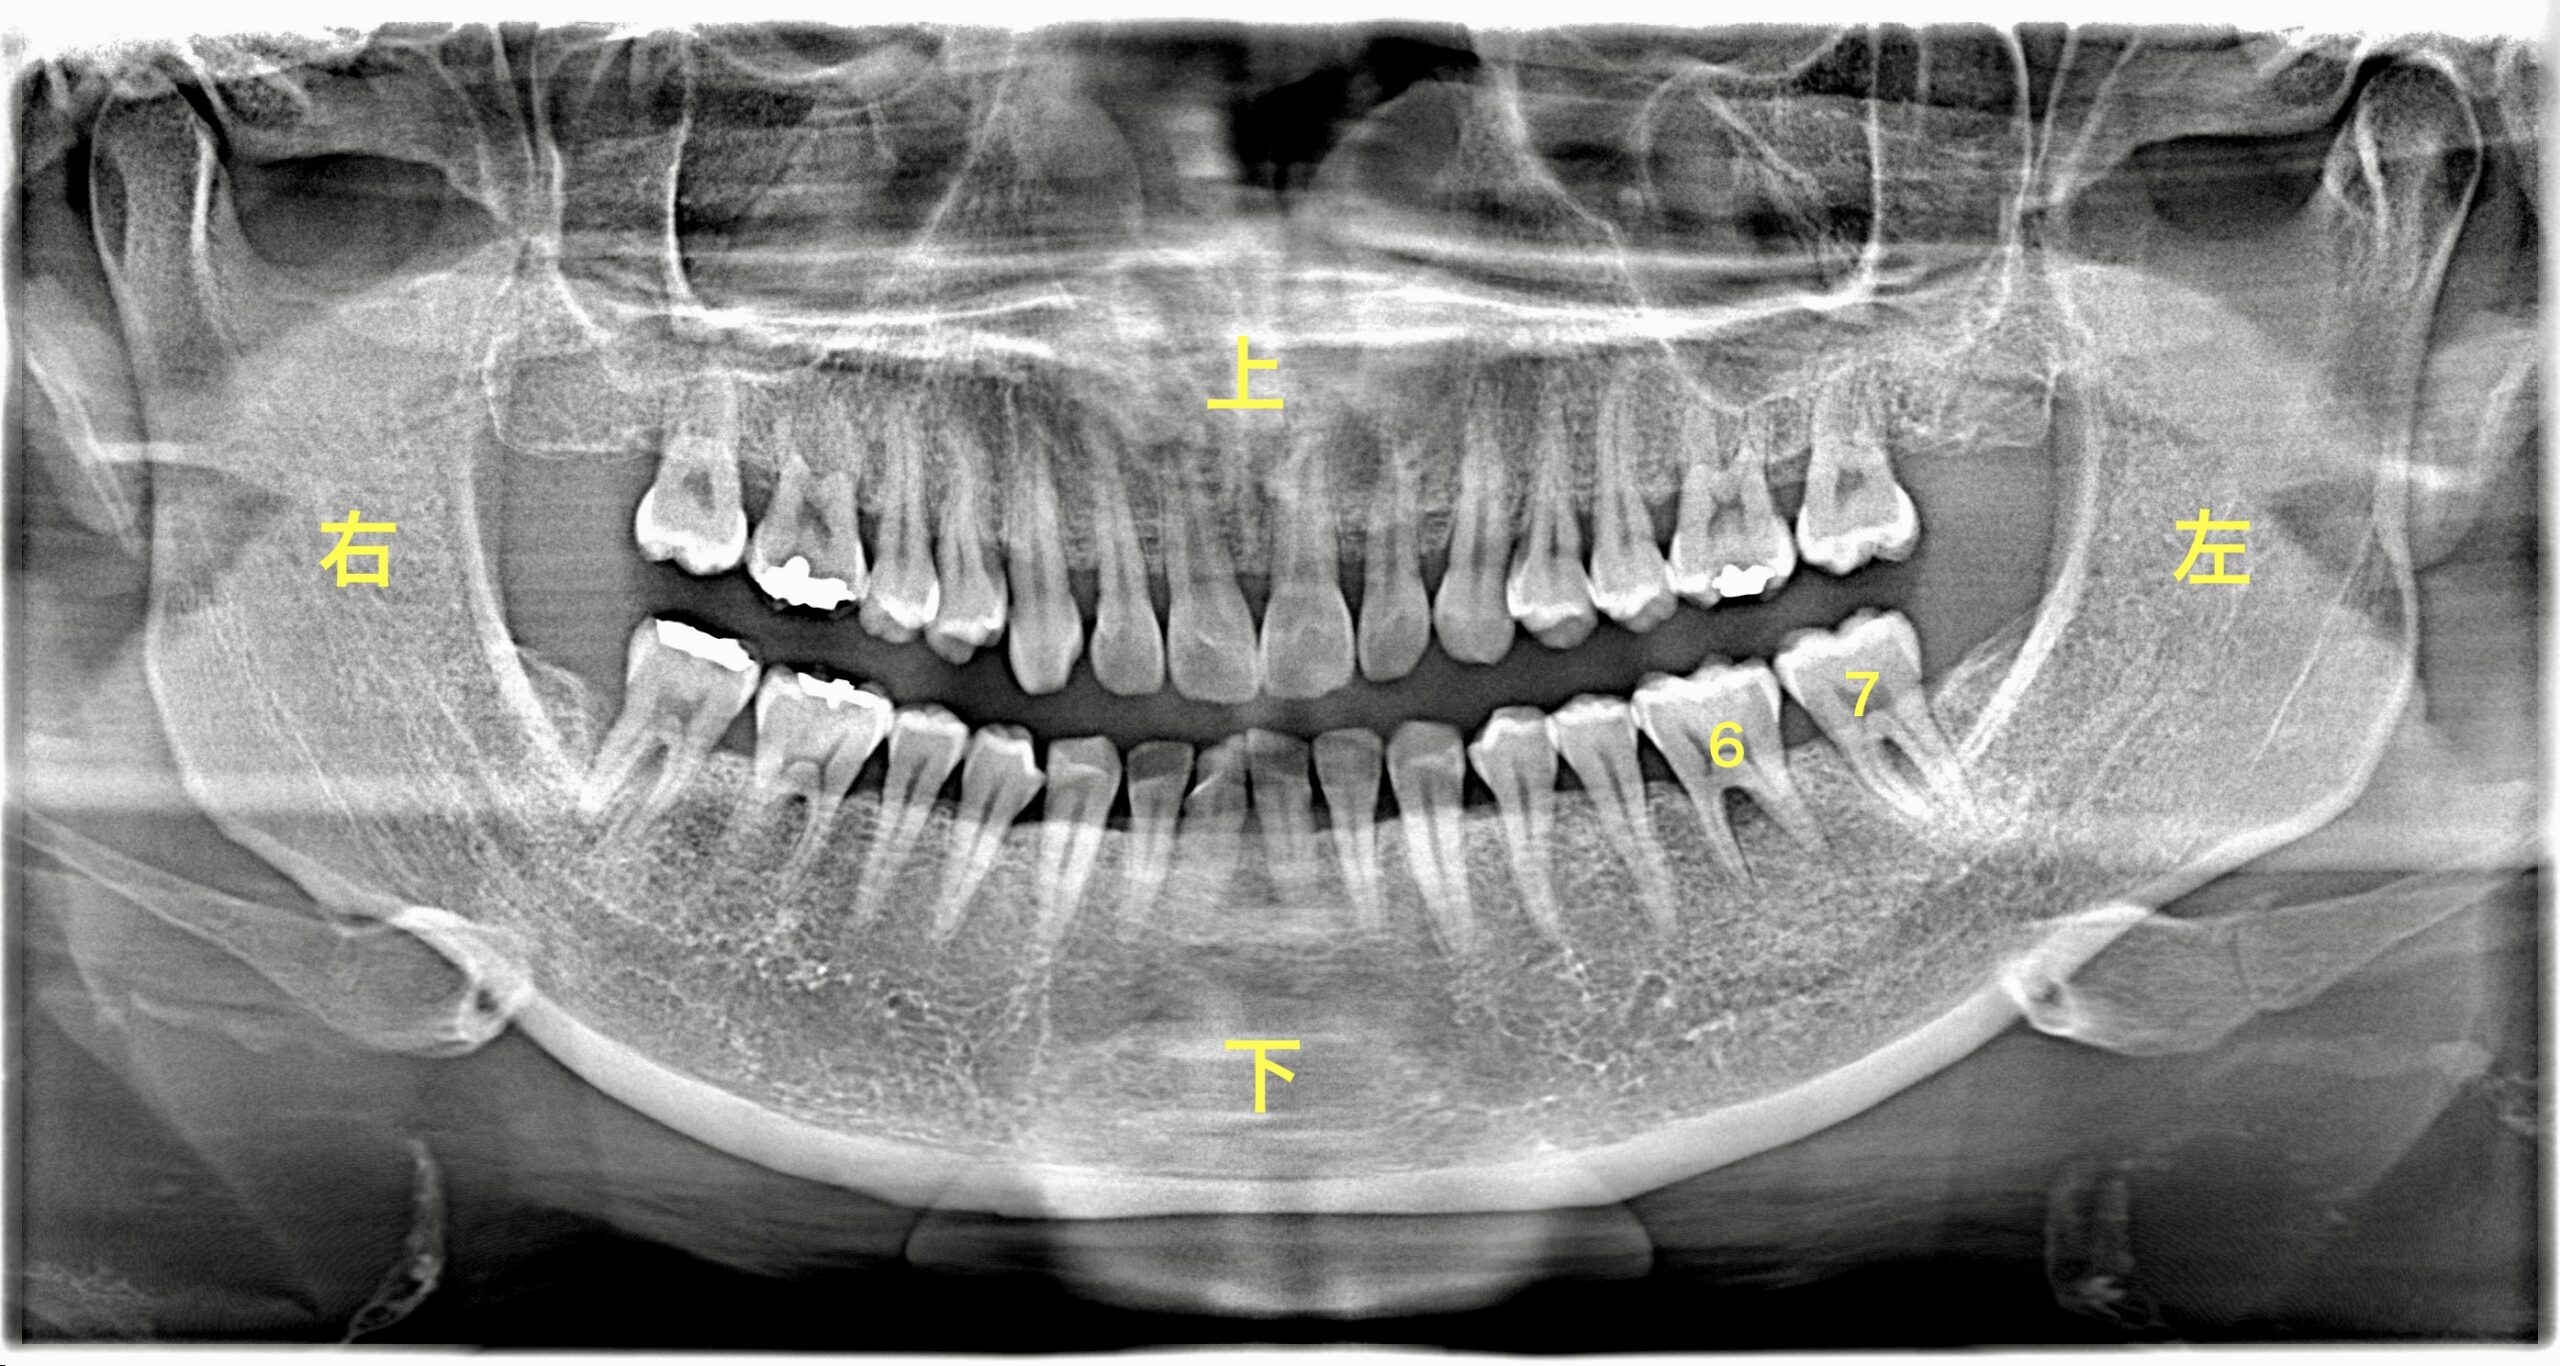

• 部位: 左下の奥歯(6番・7番)

1. 術前の検査(レントゲン)

レントゲン写真を見ると、歯の根の周りの骨がくさび状に黒く影になっているのが分かります。これが骨が溶けているサインです。

今回の左下6、7番のケースのように、適切な処置を行うことで歯の寿命を延ばすことができます。